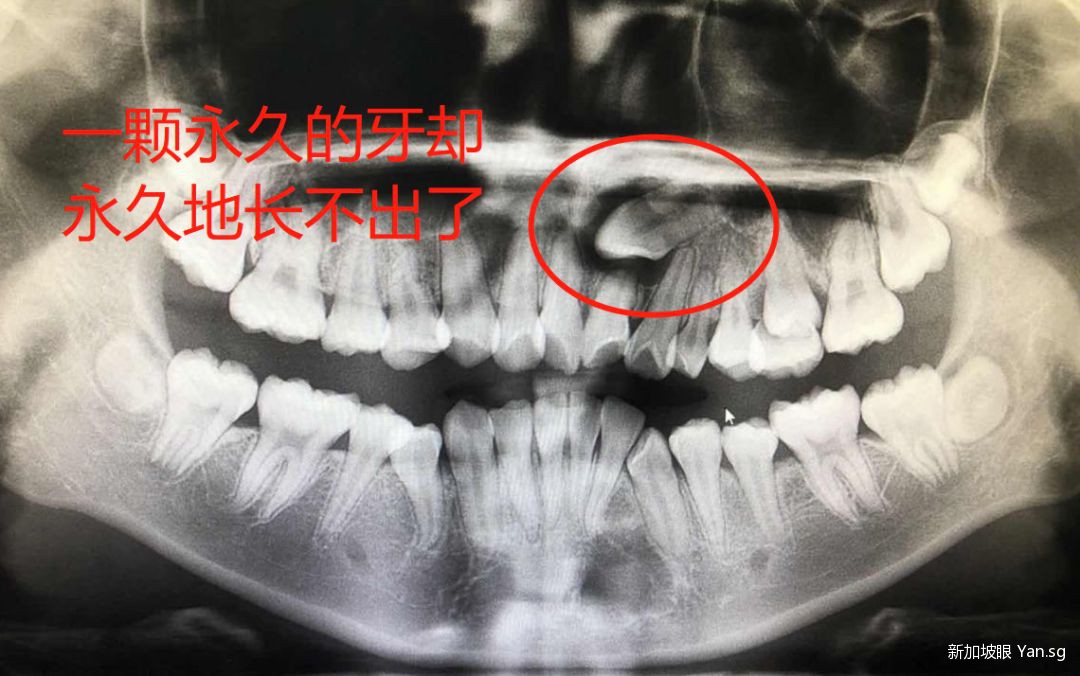

医生的经验有多重要呢。例如下面这种 impacted canine手术,矫正难度比较大。

普通的医生可能会知难而退,而经验丰富的医生,则会得心应手。